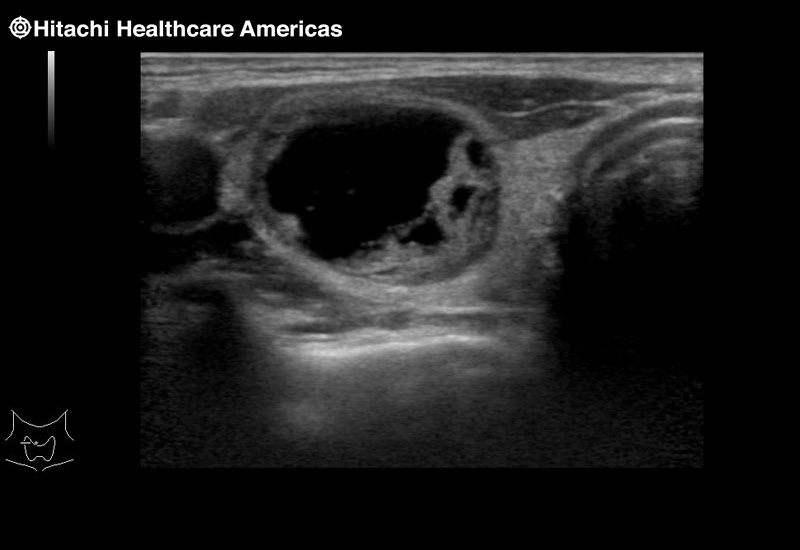

Arietta 70

Recognized for our outstanding image quality, outstanding system reliability and intuitive use of cutting edge technology, Fujifilm Healthcare remains the standard in the field of Surgery.

Learn moreArietta 70

Recognized for our outstanding image quality, outstanding system reliability and intuitive use of cutting edge technology, Fujifilm Healthcare remains the standard in the field of Surgery.